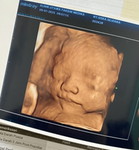

Ibu hamil

VàngIbu hamil